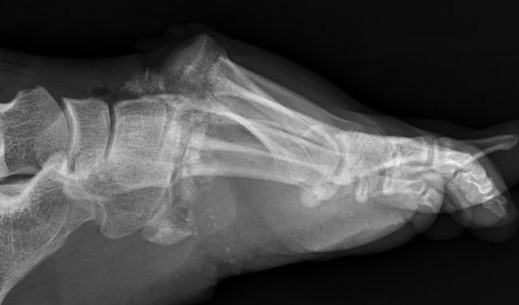

X-ray

AP / Assess medial column

Internal Oblique 30o / Assess lateral column

Lateral / assess dorsal displacement

5. Dorsal subluxation of the metatarsals

Dorsal displacement of metatarsals

Compression fractures / nutcracker of cuboid